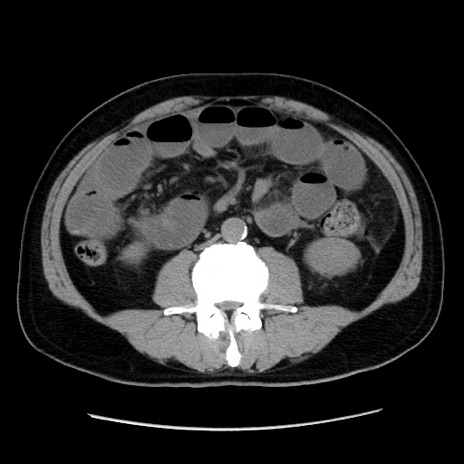

症例16(横断像)

【症例】 70歳代男性

【主訴】 腹痛、嘔吐

【現病歴】 約1ヶ月前より間欠的に腹痛と嘔吐あり、当院消化器内科を受診したところCTで多発する肝臓のLDAを指摘され、精査中であった。以降は消化器症状は安定していたが、2日前より嘔気と腹痛があり、同日より排便・排ガスが消失した。改善認めず、 本日、救急外来を受診した。

【既往歴】 大腸ポリープ切除後。

【身体所見】意識清明・会話良好、BT 36.3℃、BP 127/80mmHg、 P 80bpm、腹部:膨満あり、平坦・軟、上腹部正中および下腹部正中に圧痛あり、反跳痛なし、筋性防御なし。

【データ】WBC 7200、CRP 0.77